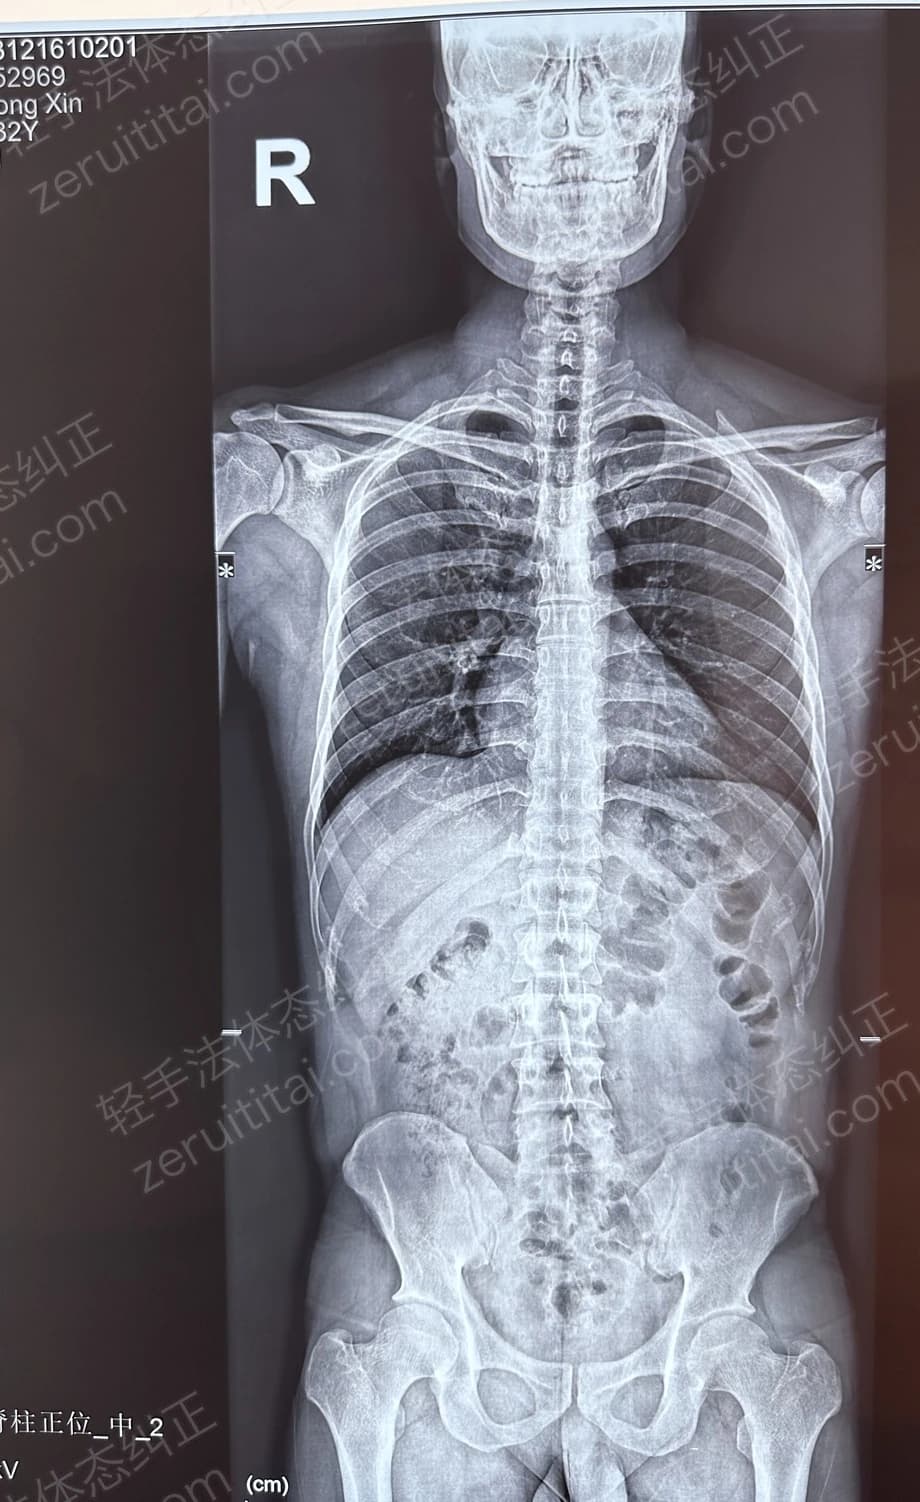

2022.12.26

第 3 次记录